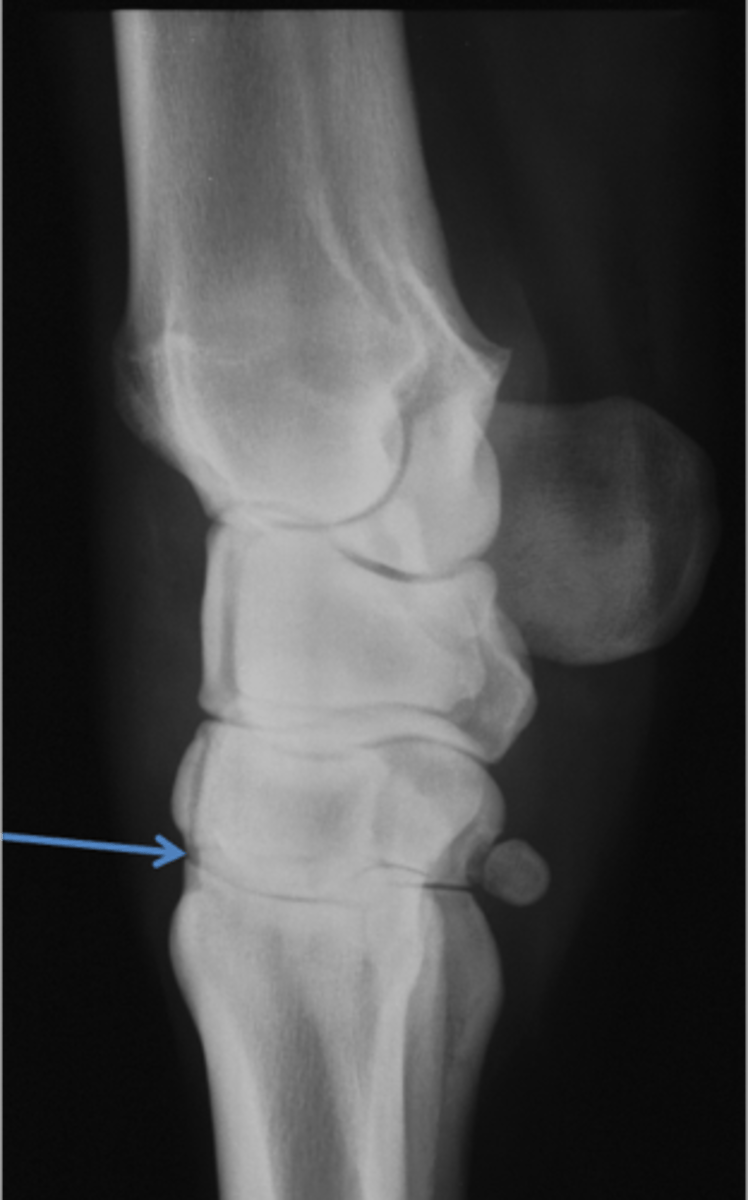

Pastern joint, LM

ID joint and view

Short pastern (P2)

Long pastern (P1)

Pastern joint (proximal interphalangeal joint)

Long pastern (P1)

Short pastern (P2)

Ergot

Collateral ligament of the coffin joint

Extensor process of P3